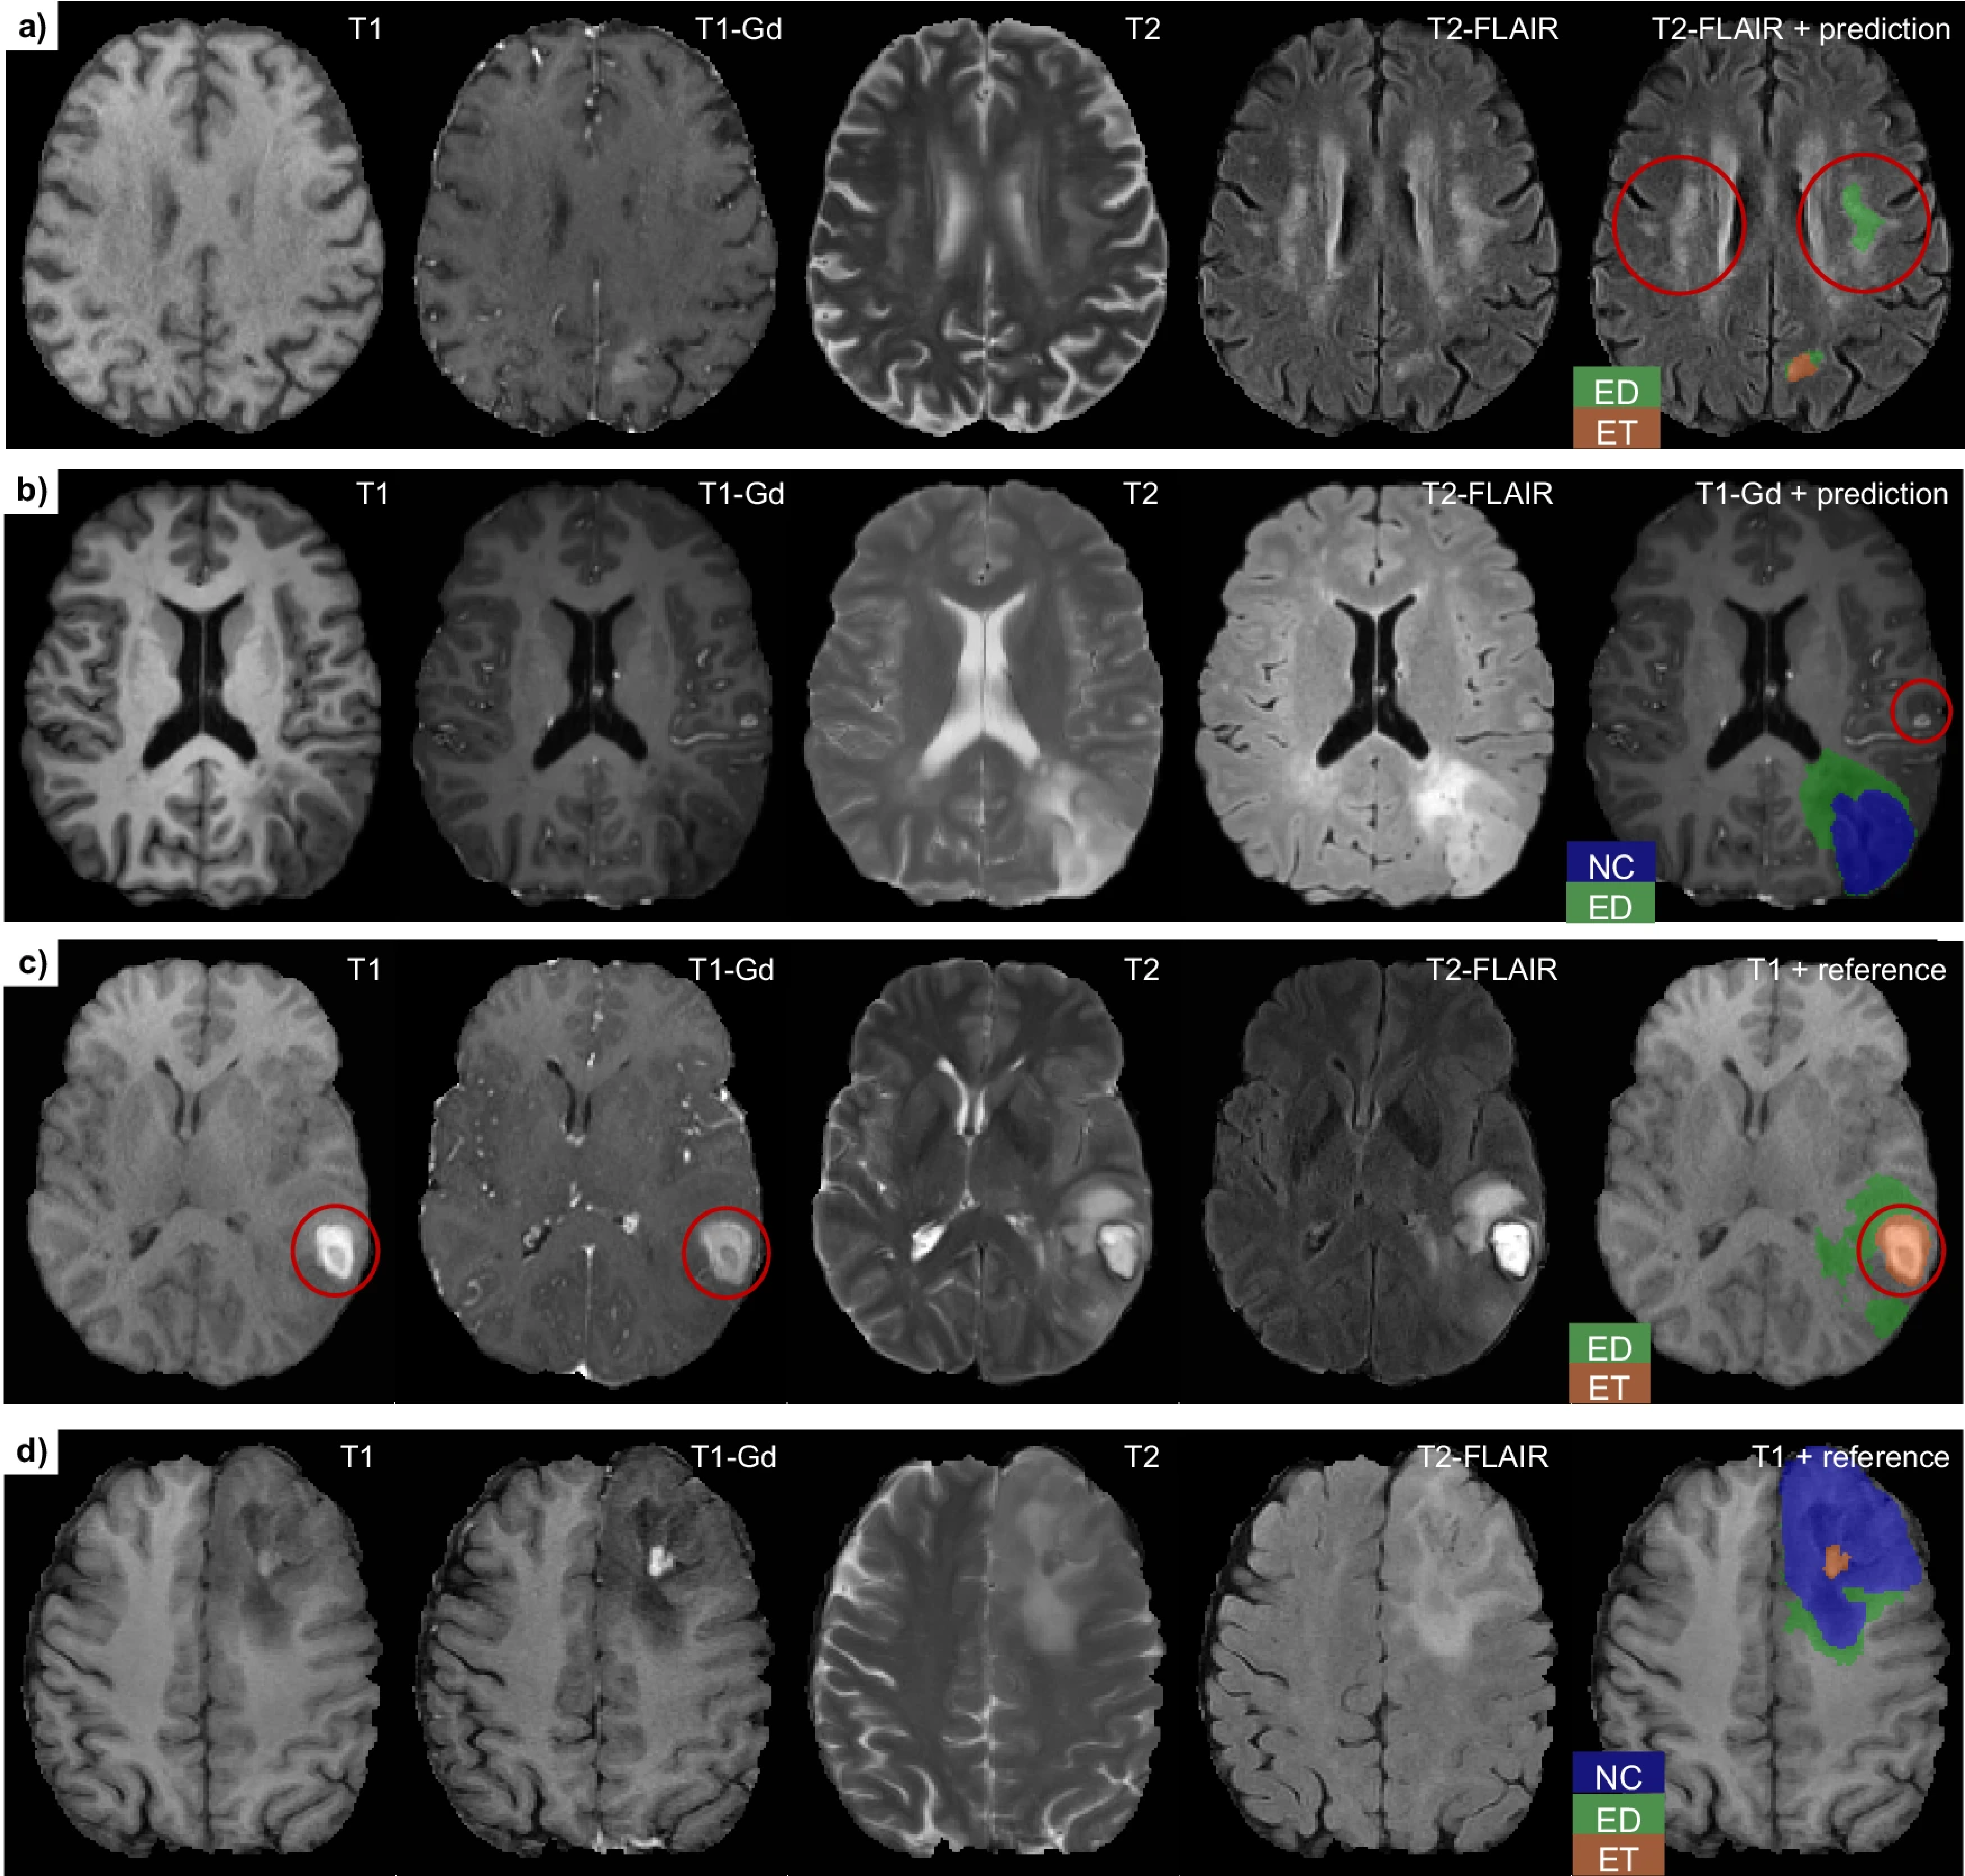

Federated AI Boosts Tumor Segmentation

FeTS Challenge benchmarks federated learning methods for secure brain tumor analysis.

Framework Personalizes Glioma Radiotherapy